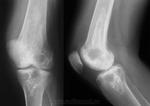

Костномозговые обызвествления обычно наблюдаются в длинных трубчатых костях - в их метафизарных или метадиафизарных отделах. Мы наблюдали их преимущественно в верхних и нижних метафизах, вернее метадиафизах, плечевых и бедренных костей. В единичных случаях встречались обызвествления костного мозга и в нижнем метадиафизе большеберцовой кости.

Рентгеновская картина обызвествлений костного мозга неоднотипна. Чаще она представляется в виде хлопьевидных теней - конгломерата, ограниченного в пределах 3 - 4 - 5 см и более, иногда в виде плотных теней, реже - более мелких вкраплений.

Обызвествления костного мозга не сочетаются с реактивными изменениями со стороны кости. Обычно не наблюдается ни периостальных наслоений, ни склерозирований структуры, остеопороза. Эти обызвествления следует относить к дистрофическому типу, т. е. к обызвествлениям, возникающим на почве дегенеративных изменений тканей. Причина дегенеративных изменений тканей костного мозга с последующими обызвествлениями не всегда ясна. В литературе имеются единичные сообщения, в которых обызвествления костного мозга на основании подходящей локализации и формы трактуются как последствия инфарктов. Можно, конечно, допустить такой генез обызвествления: последние возникают на почве некротических изменений, которые являются последствиями инфарктов. Но в практике при несомненных инфарктах, например при кессонной болезни, мы не наблюдали обызвествлений костного мозга. Костные инфаркты проявляются также выраженными деструктивными изменениями типичного вида, чего не отмечается при обызвествлениях костного мозга.

Больная 3., 58 лет, жалуется на постоянные ноющие боли в правом бедре. Видимых изменений в конечности не обнаружено. Подвижность в коленном суставе в норме. Рентгенограмма: в нижнем метадиафизе правой бедренной кости определяется конгломерат хлопьевидных плотных теней от известковых отложений размером 2 - 3 х 10 см (рис. 195, 196).

Рис. 195, Обызвествление костного мозга в нижнем отделе бедренной кости.

Рис. 196. Тот же случай в боковой проекции.

Распознавание обызвествлений костного мозга не представляет затруднений. Оно основывается главным образом на характерной картине и определенной локализации. При рентгенологическом исследовании легко определяются тени, расположенные внутри кости (в костно-мозговом пространстве), характерные для известковых отложений. Они бесформенные, в виде хлопьевидных инкрустаций, плотные. Отсутствие костной структуры отличает их от гетерогенных окостенений.

В ряде случаев тени обызвествлений костного мозга настолько характерны, что исключают дифференциацию. Тем не менее при распознавании обызвествлений костного мозга следует принимать во внимание и другие внутрикостные обызвествления, например во внутрикостно расположенных хондромах (энхондромах), в изолированном обызвествленном туберкулезном очаге (3. А. Лебедева), а также изолированные уплотнения костной структуры - крупные солитарные компактные, островки. Часто в хондромах возникают дегенеративные процессы, приводящие к кистозным образованиям, обызвествлениям и окостенениям. Обызвествления в хондромах бывают преимущественно частичными, чередующимися с участками хряща, что рентгенологически представляется просветлениями наряду с тенями известковых отложений. При энхондромах часто имеются и костные изменения утолщения кости, деформации кортикального слоя в виде истончения, выпячивания. На основании этих признаков нетрудно отличить обызвествления в хондромах от таковых костного мозга.